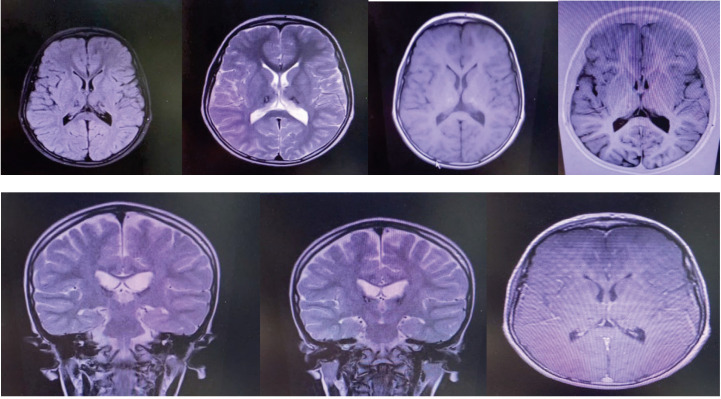

New daily data on the COVID-19 pandemic are circulating globally. This disease usually appears with respiratory symptoms such as cough, shortness of breath, and fever. The neurological complications of the disease are somewhat known in adults but rarely reported in children. Acute necrotizing encephalopathy of childhood (ANEC) is one of the brain complications associated‌ with Coronavirus disease that usually has a poor prognosis in children. In this case, we report a rare case of a 7-year-old boy who was referred to the hospital with symptoms of convulsions after contracting COVID-19 and developed cerebral necrotizing encephalopathy caused by COVID-19 infection. Although ANEC is a rare disease, clinical examination and MRI and CT scan findings play an essentialrole in diagnosing and treating the disease.‌.

Abstract Image